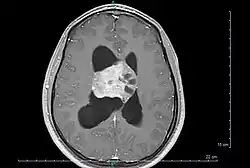

Центральная нейроцитома — чрезвычайно редкая, обычно доброкачественная внутрижелудочковая опухоль головного мозга, которая обычно образуется из нейрональных клеток прозрачной перегородки.[1] Большинство центральных нейроцитом прорастают внутрь в желудочковую систему. Это приводит к двум основным неврологическим симптомам: нечеткости зрения и повышению внутричерепного давления. Лечение центральной нейроцитомы обычно включает хирургическое удаление с вероятностью рецидива примерно в 1 из 5 случаев.[2] Центральные нейроцитомы классифицируются как grade II опухоли в соответствии с классификацией опухолей нервной системы ВОЗ.[3][4]

Центральные нейроцитомы обычно располагаются супратенториально в боковом желудочке(боковых желудочках) и/или третьем желудочке. Наиболее частым местом является передняя часть одного из боковых желудочков с последующим распространением в другой боковой и третий желудочки. Вовлечение прозрачной перегородки вероятно является особенностью опухоли.[9] Изолированное поражение третьего и четвертого желудочков встречается редко.[10]